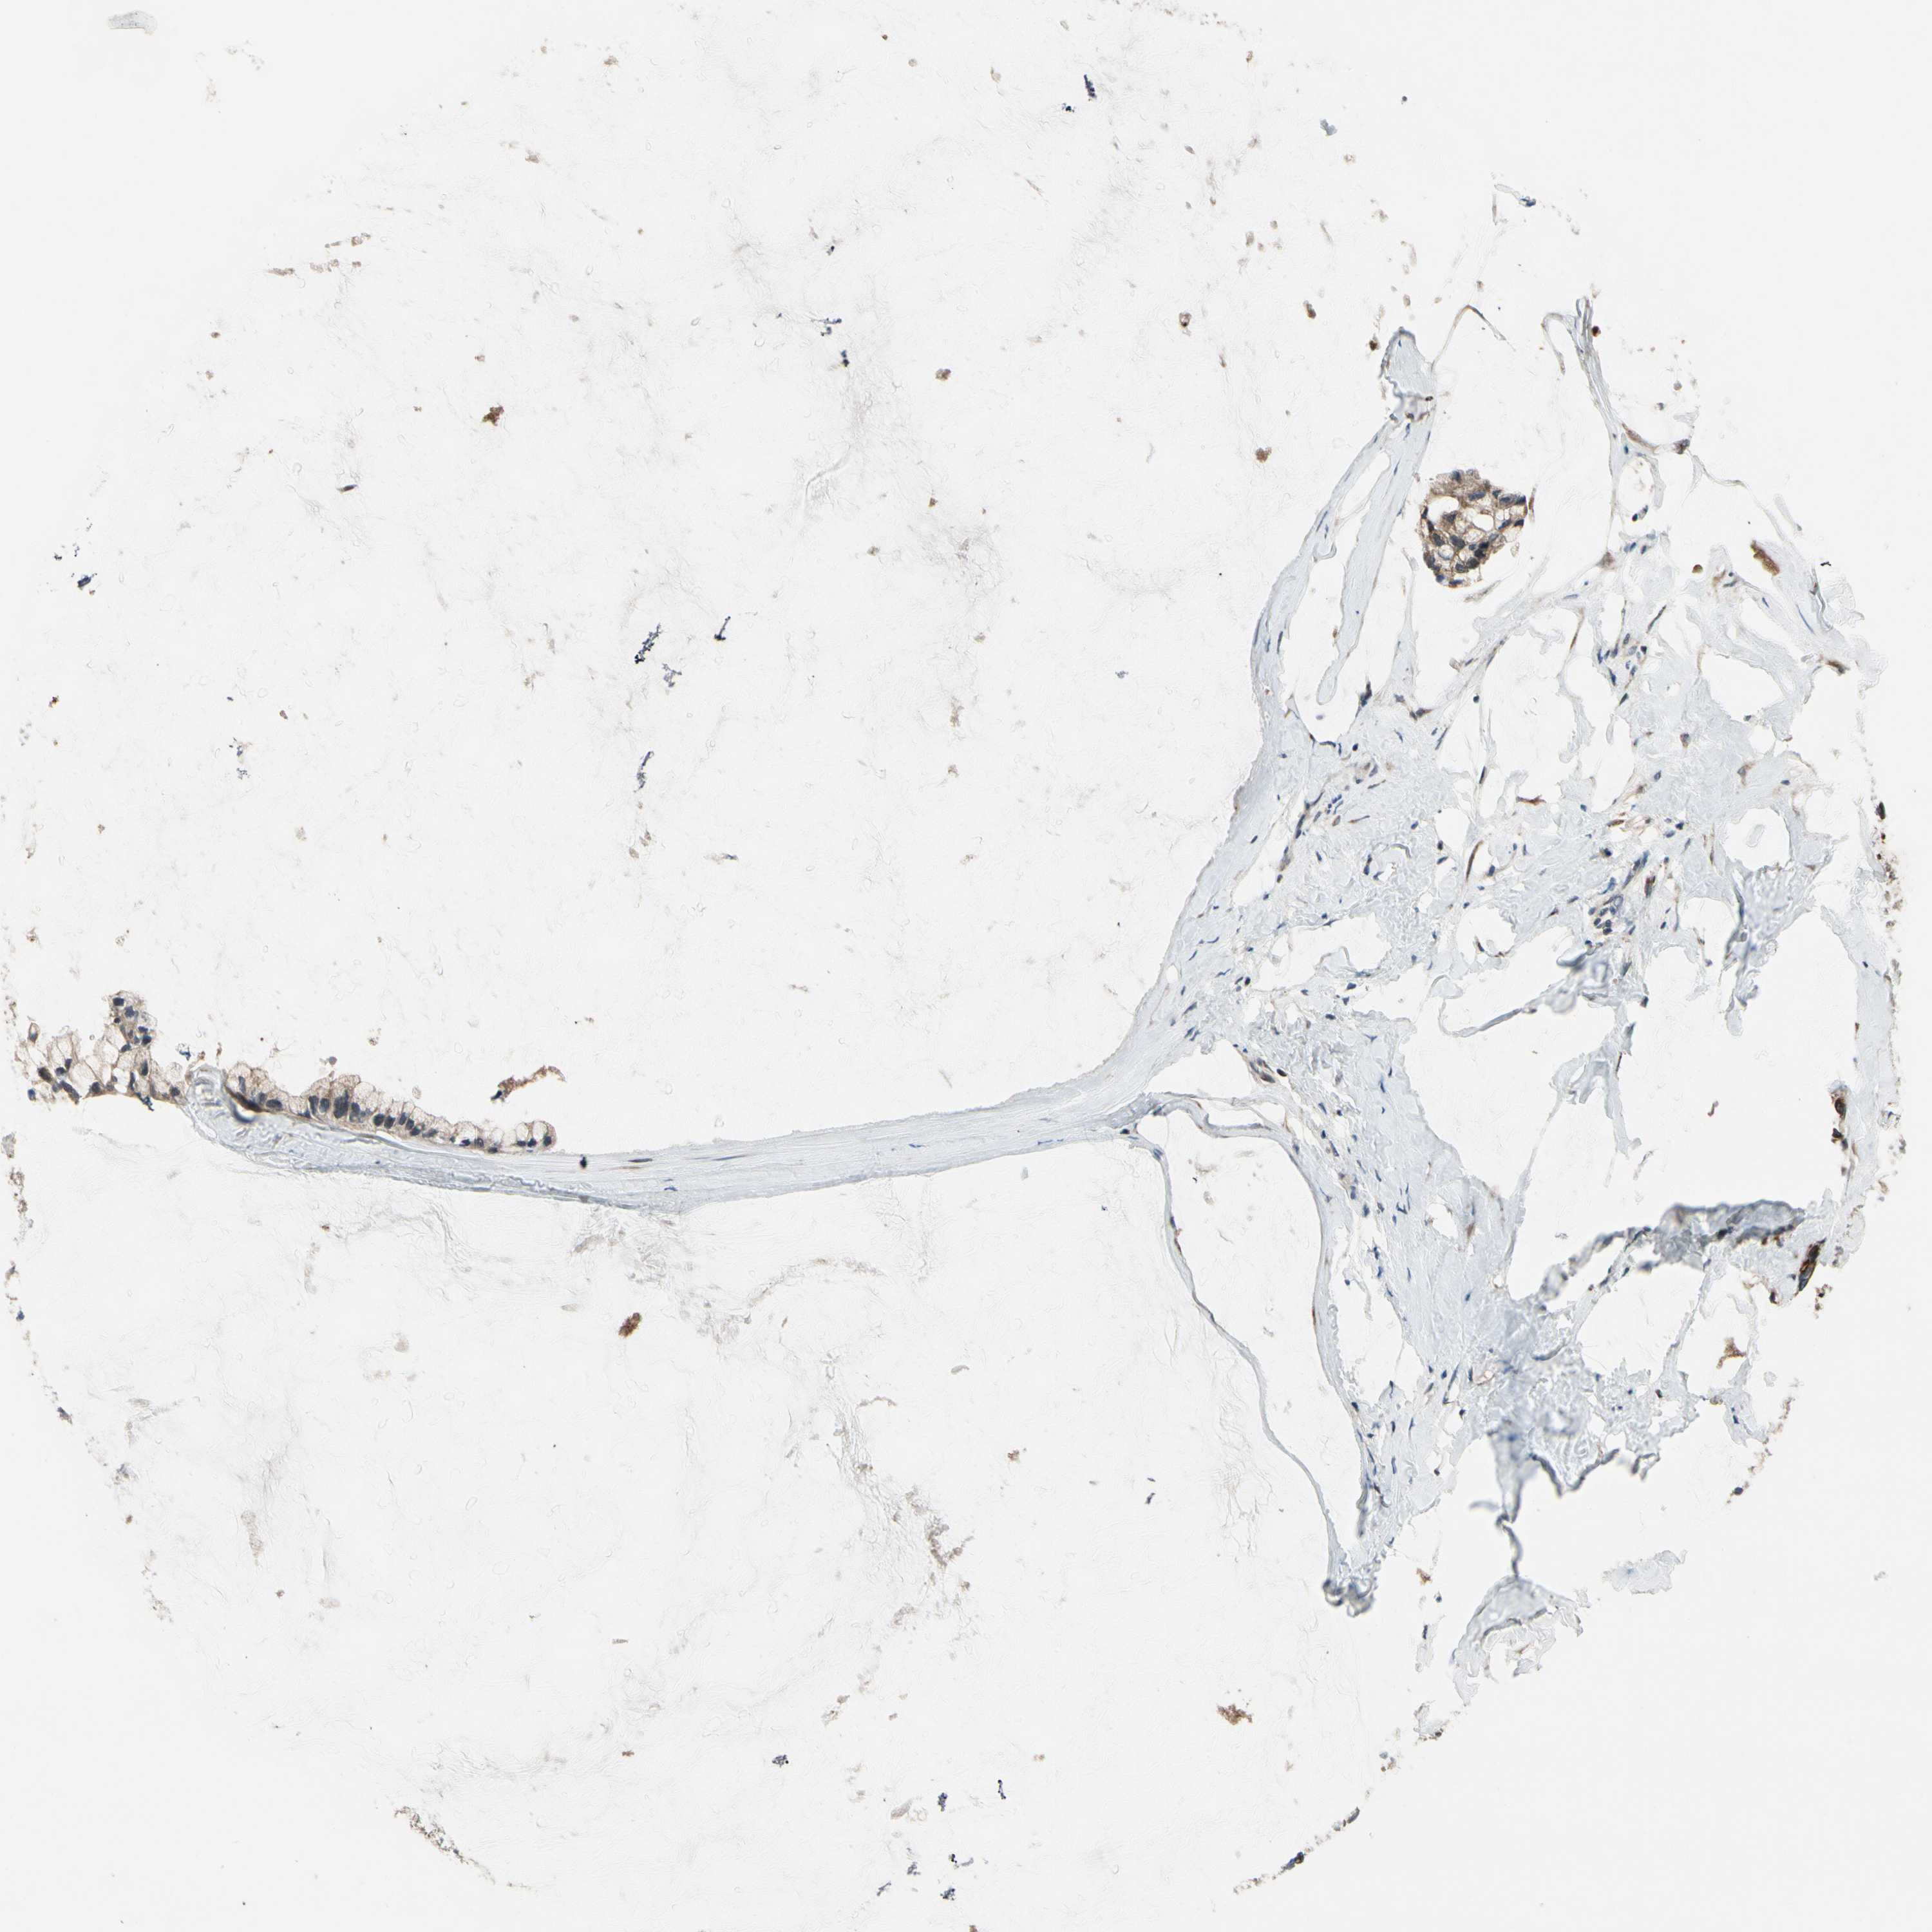

OVARIAN CANCER - Protein expressioni

A mouse-over function shows sample information and annotation data. Click on an image to view it in a full screen mode. Samples can be filtered based on level of antibody staining by selecting one or several of the following categories: high, medium, low and not detected. The assay and annotation is described here.

Note that samples used for immunohistochemistry by the Human Protein Atlas do not correspond to samples in the TCGA dataset.

Antibody stainingi

Antibody staining in the annotated cell types in the current human tissue is reported as not detected, low, medium, or high, based on conventional immunohistochemistry profiling in selected tissues. This score is based on the combination of the staining intensity and fraction of stained cells.

Each image is clickable and will lead to virtual microscopy that enables deeper exploration of all samples and also displays staining intensity scores, fraction scores and subcellular localization as well as patient and tissue information for each sample.

Antibody HPA008241

Staining

High

Medium

Low

Not detected

Intensity

Strong

Moderate

Weak

Negative

Quantity

>75%

75%-25%

<25%

None

Location

Nuclear

Cytoplasmic/membranous

Cytoplasmic/membranous,nuclear

Cystadenocarcinoma, serous, NOS

Carcinoma, endometroid

Cystadenocarcinoma, mucinous, NOS

Carcinoma, NOS